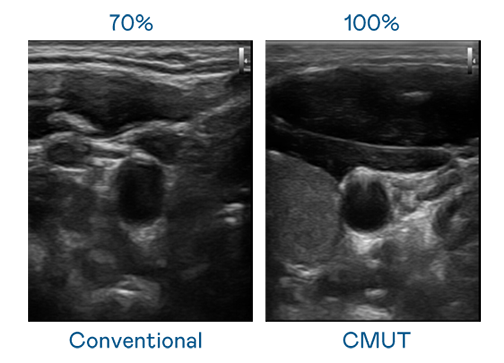

CMUT 技术是一种用电容式微机电元件来产生超音波讯号的技术。与传统 PZT 压电式技术相比,CMUT 频宽增加 30%,更宽频的超音波讯号让影像解析度大幅提升,是实现高影像品质医疗超音波扫描、促进精准医疗发展的关键技术。

大频宽带来超清晰影像

超音波影像的解析度高低,首先取决于探头能发出的讯号频宽。TVT体育 CMUT 可提供高清晰的超音波讯号,提供高频宽、高灵敏度、影像纹理细节更高的超音波影像,协助医护人员缩短影像判读时间及利用精准的医疗影像进行诊断。